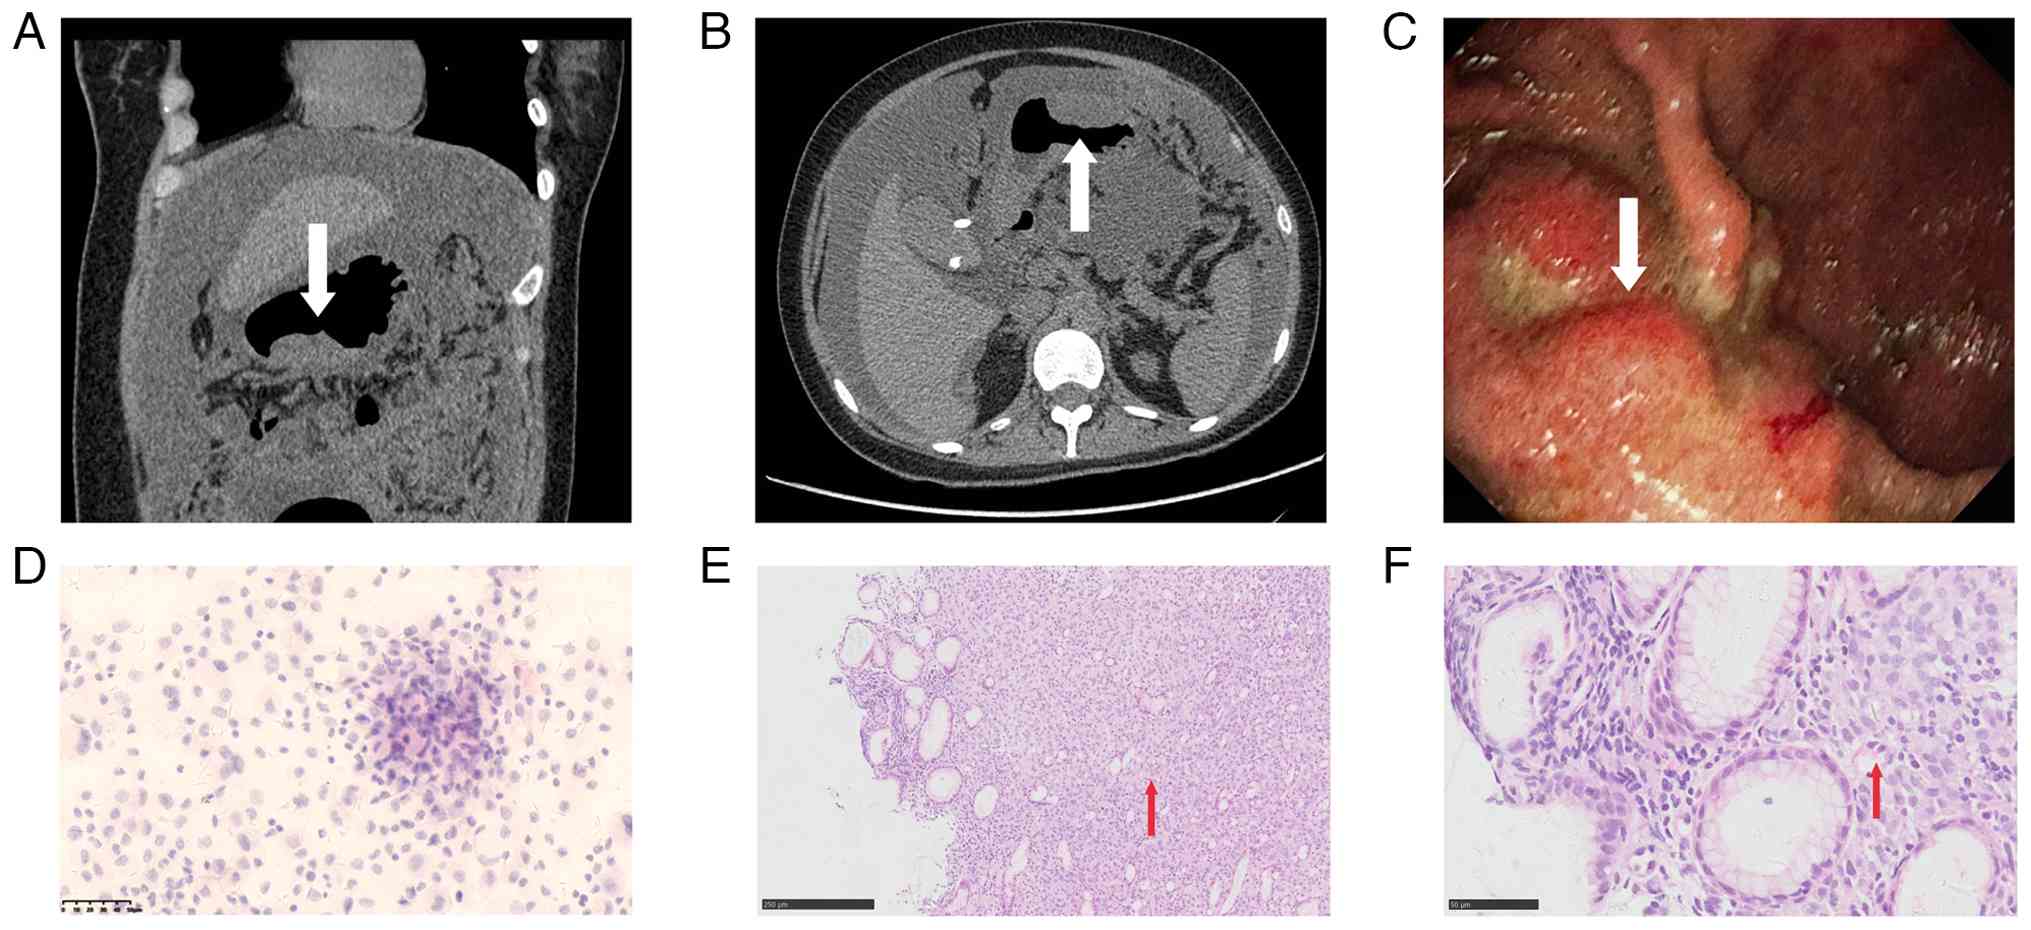

The local pathology report of the ascitic fluid showed a predominance of mesothelial cells, along with scattered lymphocytes, neutrophils and atypical cells (data not shown). Moreover, non-enhanced pelvic MRI at the local hospital revealed nodular thickening of the peritoneum, raising concerns about tumor metastasis or peritoneal tuberculosis, along with notable ascites showing fluid stratification (Fig. 1A and B). Due to limitations in diagnostic and treatment options at the local facility, the patient was referred to Peking University First Hospital for further management.

Pelvic magnetic resonance imaging and

ultrasonography showing maternal ascites and the intrauterine

fetus. (A) Coronal view and (B) transverse section of pelvic MRI,

with ascites indicated by the red arrow. (C) Abdominal ultrasound,

with ascites indicated by the red arrow. (D) Obstetric ultrasound,

with the fetus indicated by the white arrow.

Figure 1.

Pelvic magnetic resonance imaging and ultrasonography showing maternal ascites and the intrauterine fetus. (A) Coronal view and (B) transverse section of pelvic MRI, with ascites indicated by the red arrow. (C) Abdominal ultrasound, with ascites indicated by the red arrow. (D) Obstetric ultrasound, with the fetus indicated by the white arrow.

On physical examination, the patient presented with abdominal distension, dullness on percussion, an abdominal circumference of 104 cm, an indistinct uterine fundus and a fetal heart rate of 150 bpm. Laboratory investigations revealed a normal hemoglobin level (136 g/l) (ref. 115–150 g/l) but notable ketosis (+4) (ref. negative) on urinalysis. Biochemical tests showed an albumin level of 35.5 g/l (ref. 35–50 g/l). Notably, tumor markers were elevated, including α-fetoprotein at 36.74 ng/ml (ref. ≤10 ng/ml), cancer antigen 15–3 at 17.49 U/ml (ref. ≤30 U/ml), cancer antigen 72–4 at 14.64 U/ml (ref. ≤6.9 U/ml), cancer antigen 19–9 at >1,000 U/ml (ref. ≤37 U/ml), cancer antigen 125 at 1,040 U/ml (ref. ≤35 U/ml), carcinoembryonic antigen at 180.30 ng/ml (ref. ≤5 ng/ml) and neuron-specific enolase at 11.51 ng/ml (ref. ≤16.3 ng/ml). Tests for tuberculosis were negative. Obstetric ultrasound confirmed an intrauterine pregnancy with a viable fetus and showed a large amount of free fluid in the pelvic and abdominal cavities, ~90 mm in depth and with no abnormalities in the bilateral adnexa. Abdominal ultrasound further showed thickened greater omentum, notable ascites with a maximum depth of ~93 mm (Fig. 1C and D).